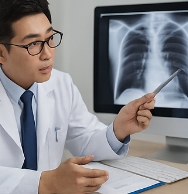

폐암 초기증상이 의심된다면 지체하지 말고 병원에서 검진을 받아야 합니다.

- 흉부 X-ray 검사: 폐 구조 확인.

- 저선량 CT 검사: 조기 폐암 진단에 효과적.

- 세포검사: 가래나 기관지 세포를 검사해 암세포 여부 확인.

폐암 초기증상 발견 시 빠른 진단이 생존율을 크게 높입니다.